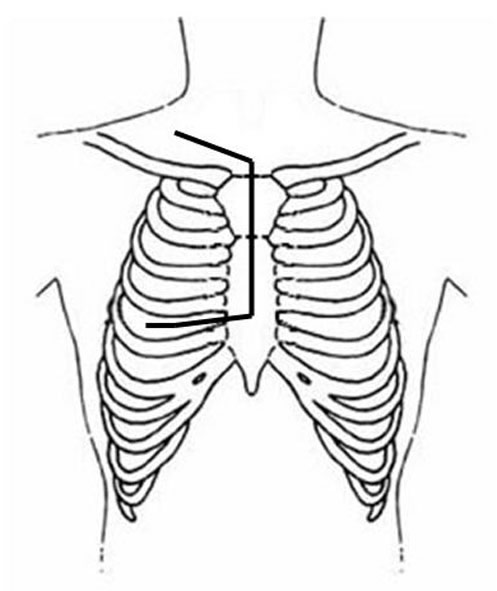

Several surgical approaches have been described for Pancoast tumor, ranging from posterior access [11] to anterior accesses [15-17], alone or in combination. The classic posterior approach popularized by Paulson and Shaw [11] gives excellent exposure of the posterior chest wall but does not allow safe, direct visualization and manipulation of more anterior anatomical structures forming the thoracic inlet. In particular, the management of invaded subclavian vessels (particularly the subclavian vein) is difficult and dangerous, often requiring an anterior approach. Therefore, a detailed knowledge of the anatomy of the apex of the chest and lower neck (Figure 3) and the availability of alternative approaches in their armamentarium are essential for surgeons managing these tumors.

| Figure 3: Diagram of the thoracic inlet from a left lateral view. | Figure 4: The Pancoast tumor can invade the thoracic inlet in a posterior (A), middle (B) or anterior (C) site. |